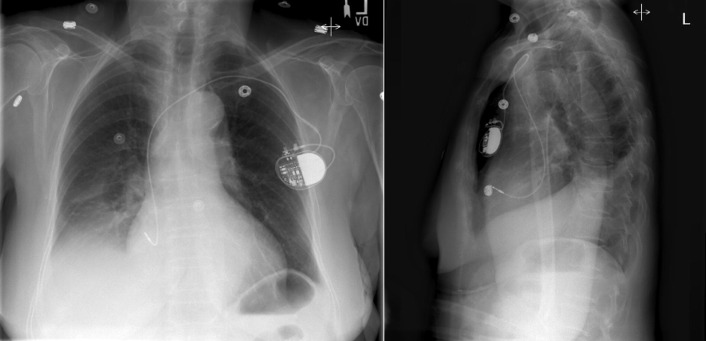

Chest radiography has a standard role in the identification of several potential complications such as pneumothorax, hemothorax, and several forms of malposition after insertion of pacemakers, implantable cardioverter defibrillators (ICDs), and cardiac resynchronization therapy devices.

Pacemaker leads are apparent, and ICDs are more obvious because of their larger coils. Coronary sinus leads for cardiac resynchronization therapy are finer leads.

Endocardial Pacer Leads

The position and integrity of endocardial pacer leads should be verified, especially when pacemaker dysfunction is clinically suspected ( Graphics 23-1 to 23-4 ; Figs. 23-1 to 23-15 ).The most common cause of pacemaker dysfunction that is apparent on the chest radiography is distal lead displacement/misplacement.

With a right atrial lead , the tip should be in the right atrial appendage.

With a right ventricular lead , the tip should lie anteriorly at the apex of the heart.